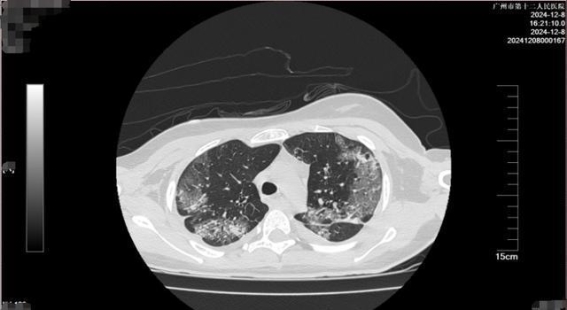

转运过程中,小美的生命体征几乎无法测量,心率急剧飙升至189次/分钟,血压已经无法测定,血氧饱和度也处于极低水平。广州医院在接诊的第一时间,启动了绿色通道,迅速为她进行了全面检查。经过紧急评估后,医生们决定实施个性化的治疗方案,包括精细化液体管理、血液净化、肺保护及脑保护措施等。整个过程极其紧张,医生们争分夺秒,为小美的生命展开了一场生死较量。

经过了2小时的紧急治疗后,小美的生命体征逐渐恢复稳定,血压和心率逐步上升。病情依旧严峻。小美的全身仍然出现了凝血功能异常,多个器官功能衰竭,中毒性脑病的症状十分明显。她全身各部位出现了渗血,特别是口腔、咽喉及气道内出血明显,这使得气管插管等医疗操作变得极其困难。但即便如此,重症医学科的团队始终没有放弃,对她实施全方位治疗。

专家表示,急性“敌草快”中毒的严重程度与摄入剂量有着直接关系。小美的情况,属于重度中毒。根据现有的医学理论和治疗经验,摄入少量敌草快的患者,可能仅出现轻微的肾功能损伤,并能完全恢复;而中度中毒则可能导致急性肾衰竭等多脏器功能障碍,三分之二的患者能够康复;但是一旦摄入超过一定剂量,患者会迅速进入多脏器衰竭阶段,死亡率极高。